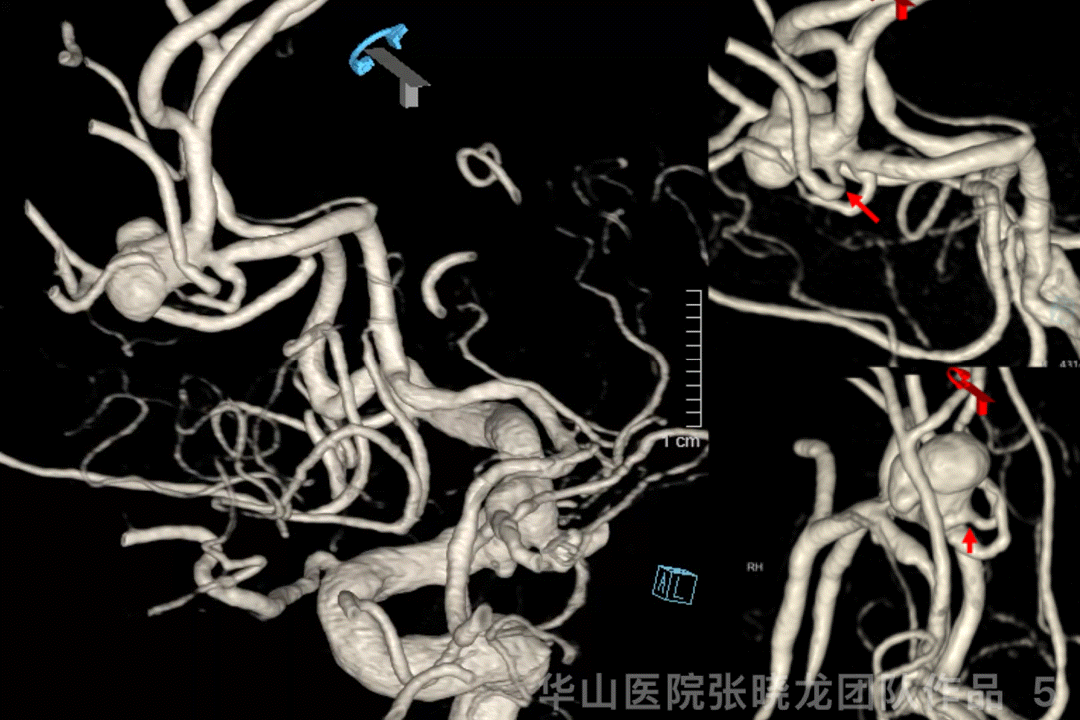

Figure 5 GIF. 3D reconstructions showed the three aneurysms all irregular and a branch originating from the A2/3 aneurysm neck, which should be preserved intra-operatively.